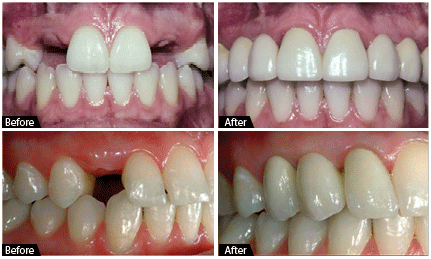

Fixed partial dentures are a permanent solution to replace missing teeth, offering the look, feel, and function of natural teeth. Unlike removable dentures, they are securely attached using dental implants or tooth, so you can eat, speak, and smile with confidence — no slipping or clicking.

These dentures restore your bite strength, improve facial appearance, and are custom-designed to fit comfortably in your mouth. They’re ideal for patients seeking long-term comfort, stability, and a natural-looking smile.

Removable dentures are a cost-effective and non-invasive way to replace missing teeth. Designed to fit comfortably in your mouth, they help restore your ability to chew, speak, and smile confidently.

These dentures can be taken out for cleaning and while sleeping, making them easy to maintain. Whether you’re missing a few teeth (partial dentures) or all teeth (complete dentures), removable options are custom-made for a secure and natural-looking fit.